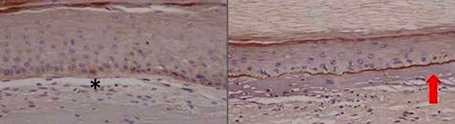

Mejoran la eficacia y precisión de la edición genómica para el tratamiento de la epidermólisis bullosa

Mejoran la eficacia y precisión de la edición genómica para el tratamiento de la epidermólisis bullosa. La epidermólisis bullosa o enfermedad de la piel de mariposa se caracteriza...

Edición genómica para la epidermólisis bullosa: un poco más cerca de la clínica

Edición genómica para la epidermólisis bullosa: un poco más cerca de la clínica La epidermólisis bullosa distrófica recesiva o piel de mariposa es una enfermedad rara de fragilidad...